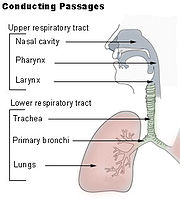

Acute viral nasopharyngitis, or acute coryza, usually known as the common cold, is a highly contagious, viral infectious disease of the upper respiratory system, primarily caused by picornaviruses (including rhinoviruses) or coronaviruses.

The virus enters the cells of the lining of the nasopharynx (the area between the nose and throat), and rapidly multiplies. The major entry point is normally the nose, but can also be the eyes (in this case drainage into the nasopharynx would occur through the nasolacrimal duct).